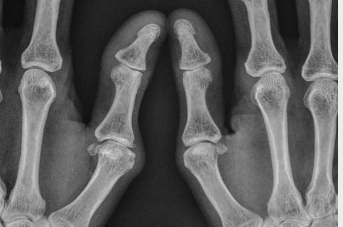

- X-ray 검사 : 연골 손상, 관절 간격 감소, 뼈 돌기 등을 확인할 수 있어요.

- MRI : 필요할 때 더 정밀하게 연골 상태를 체크해요.